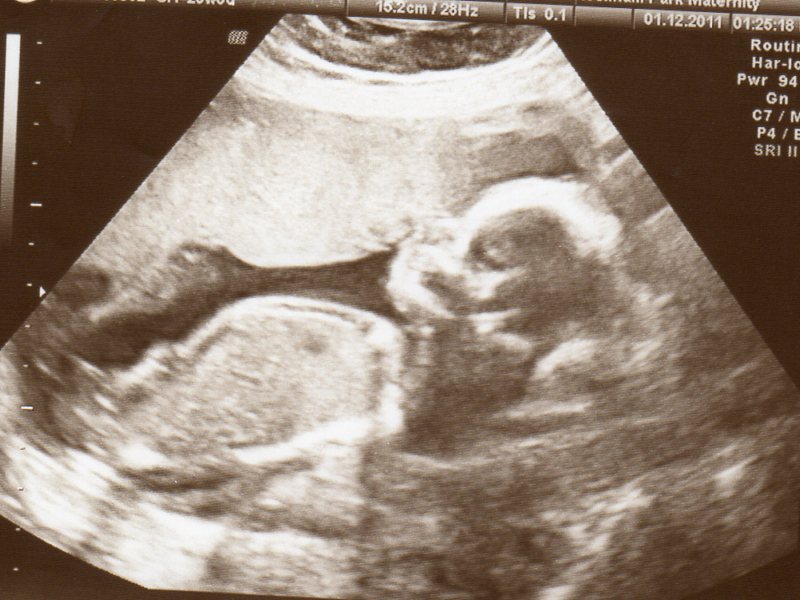

Let's see how many are right. :) Attachment 13130

Oooh, baby looks pretty curled at the bottom there:) I would hazard a guess of girl! What gestation is baby??